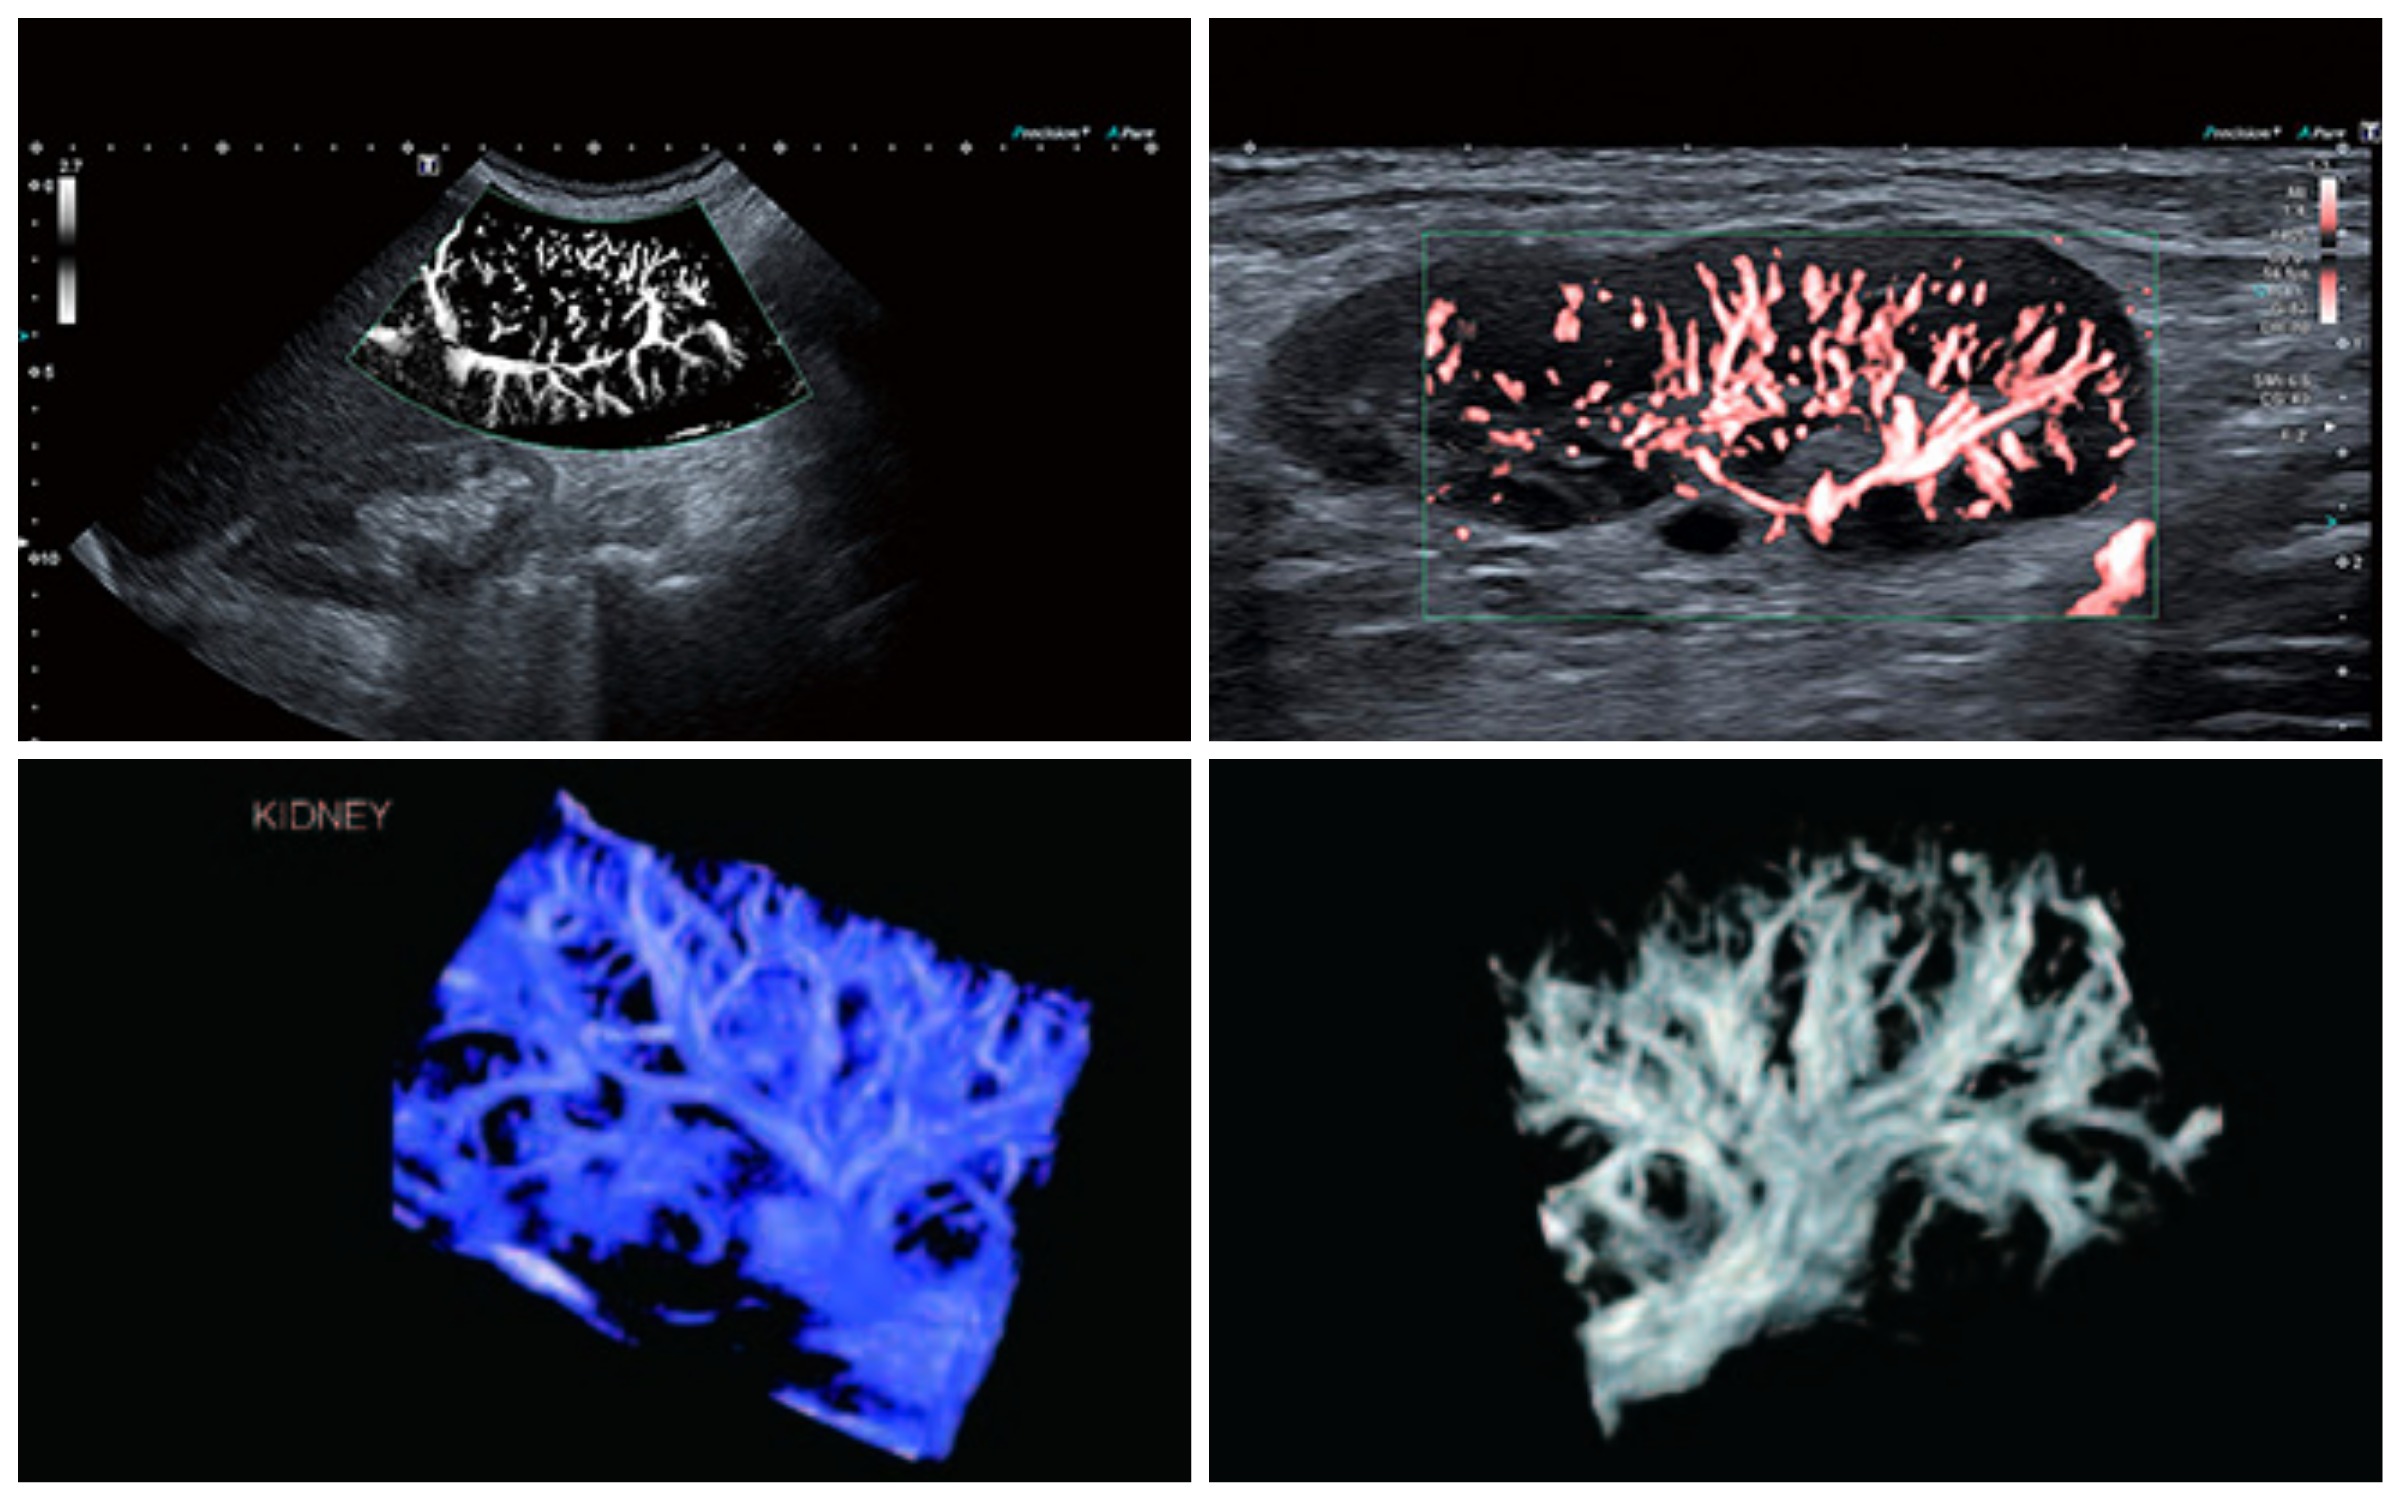

На сьогоднішній день завдяки впровадженню найсучасніших методів паралельної візуалізації і алгоритмів штучного інтелекту магнітно-резонансні томографи Canon Medical здатні задовольнити запити лікарів і оптимізувати тривалість дослідження до 5 хвилин без втрати якості.